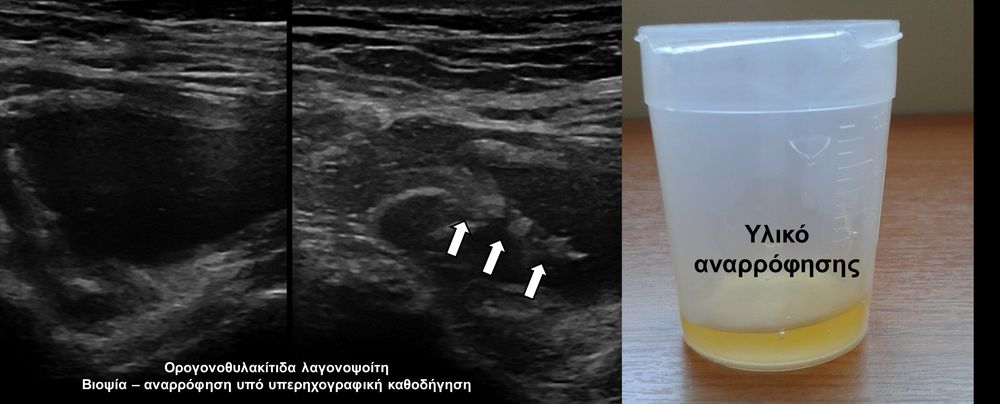

Η οστική βιοψία και η βιοψία όγκων μαλακών μορίων χρησιμοποιείται για την ιστολογική διάγνωση αλλοιώσεων (καλοήθων - κακοήθων / πρωτοπαθών ή μεταστατικών) ή για τη λήψη υλικού προς καλλιέργεια ώστε να αναδειχθεί το μικρόβιο που προκαλεί τη λοίμωξη του μυοσκελετικού συστηματος (πχ σπονδυλοδισκίτιδα). Η βιοψία υπό συνεχή απεικονιστική καθοδήγηση συμβάλλει στην υψηλή ακρίβεια τοποθέτησης της βελόνης εντός της βλάβης με ασφαλή προσπέλαση. Η χρήση σύγχρονων ομοαξονικών συστημάτων βιοψίας (coaxialtechnique) επιτρέπει την λήψη πολλαπλών δειγμάτων με μια μόνο παρακέντηση.